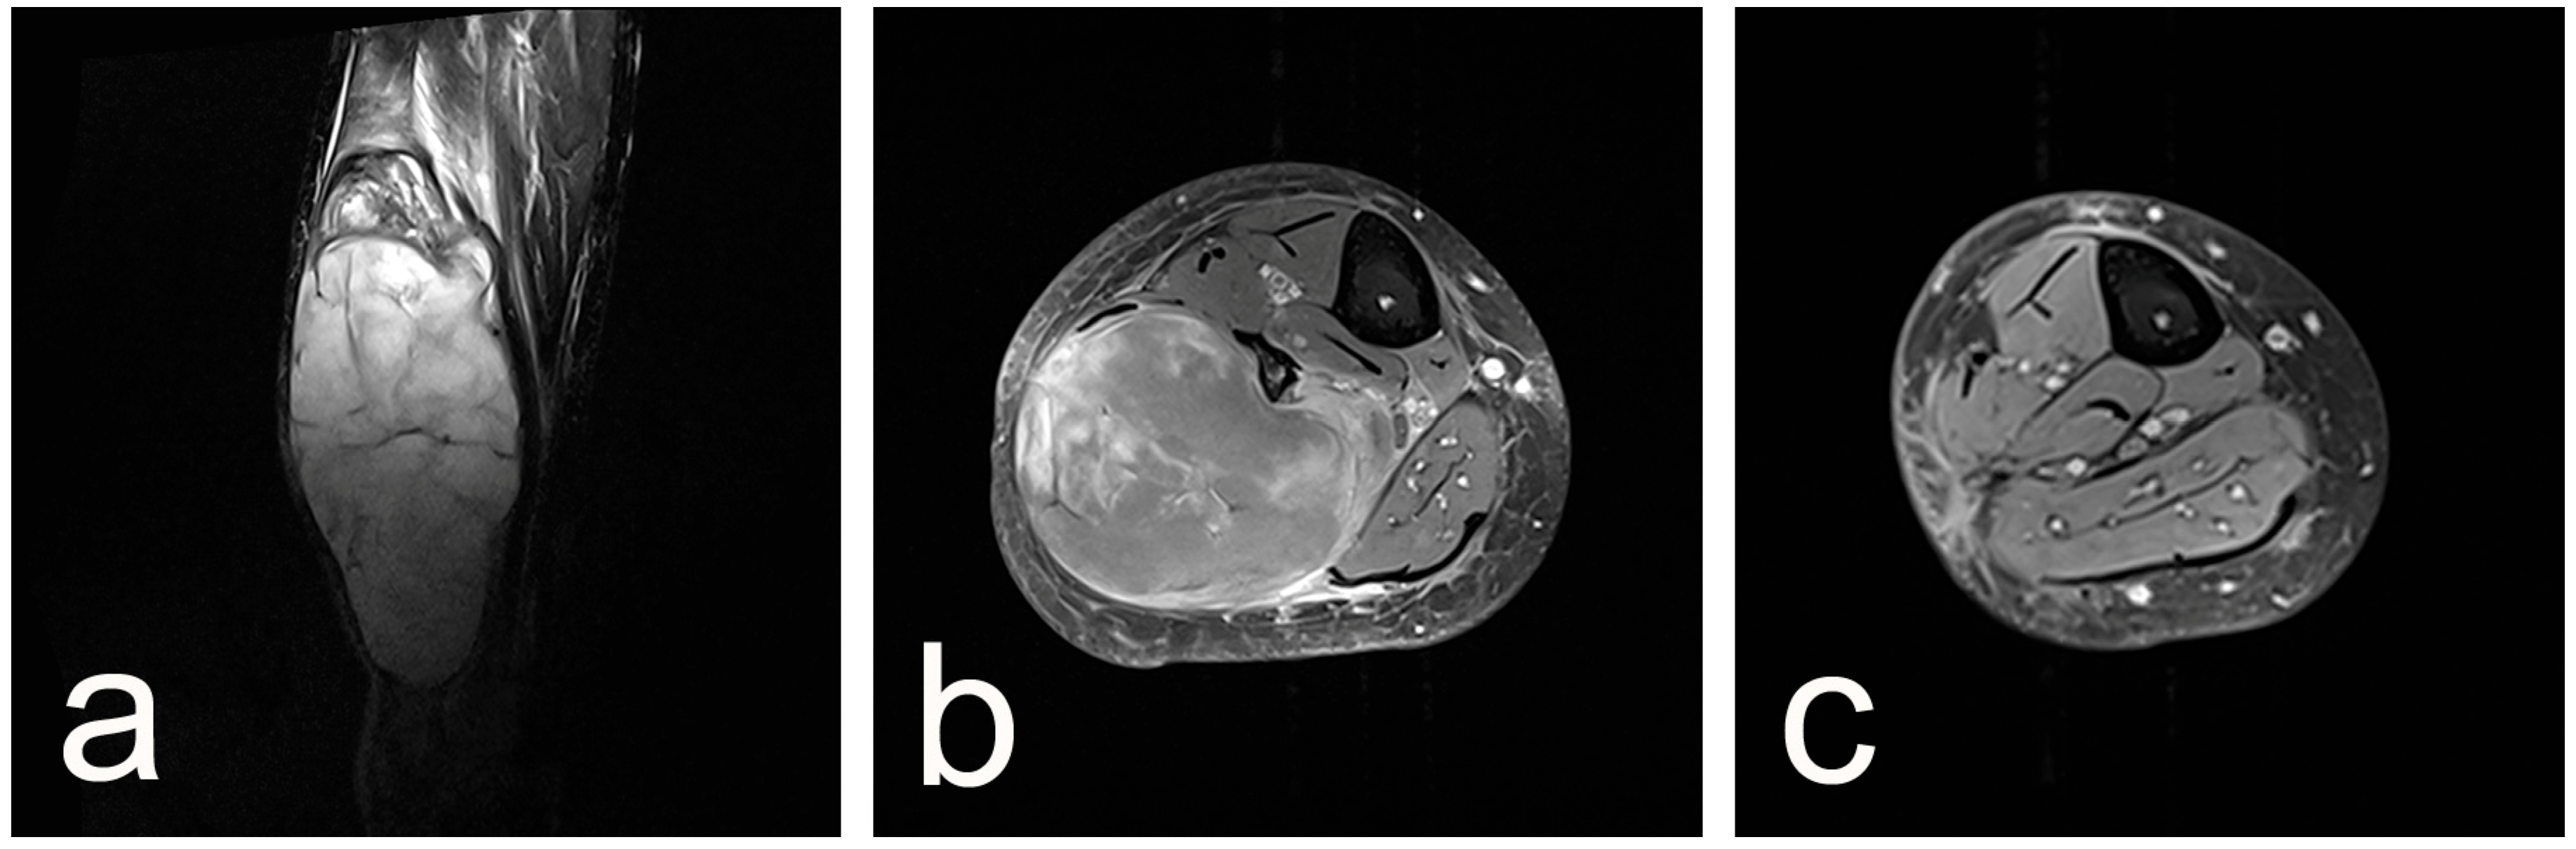

2. Case Presentation